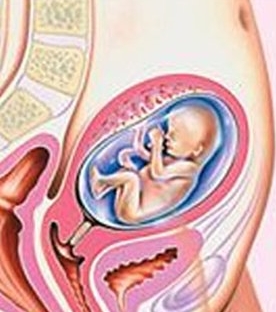

Расположение плода на 15-й неделе беременности: фотографии и иллюстрации